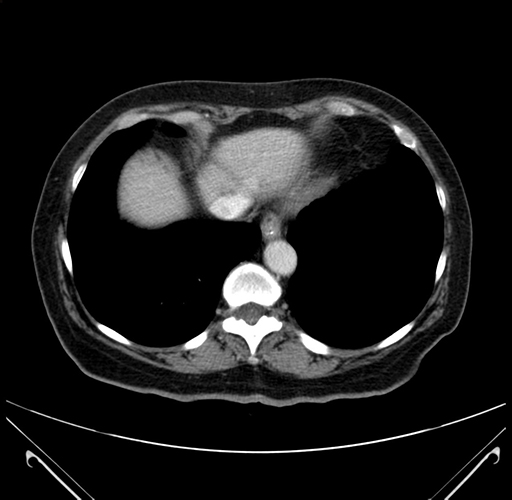

Pre-Chemo: Axial Venous

Pre-Chemo: Coronal Venous

Axial Venous

Coronal Venous

Imaging analysis

Based on your CT findings, which issue(s) would give reason for "planned slowing down moment(s)" in this case?

Considering a standard right hepatectomy procedure, what step(s) of the operation would you do differently in this case?